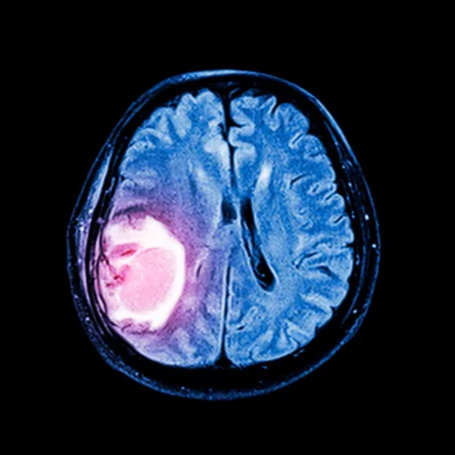

Tumores Cerebrales

Diagnóstico: Incluye resonancia magnética (RM), tomografía (TAC), estudios neurológicos y, en muchos casos, biopsia para confirmar el tipo y grado del tumor.

Tratamiento: Depende del tipo, tamaño y ubicación. Puede incluir cirugía para extirpar el tumor, radioterapia, quimioterapia o terapias dirigidas. La cirugía busca reducir el tamaño tumoral y aliviar síntomas.